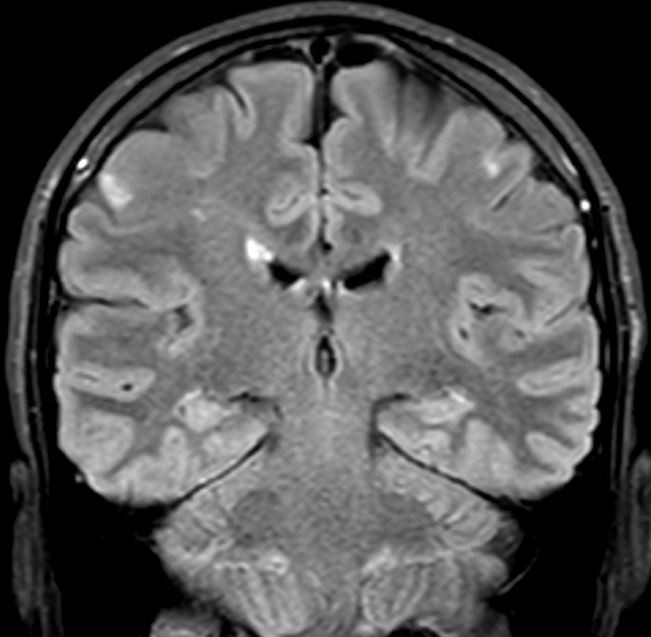

Diffusjonsvektet MR-undersøkelse viste små, ferske infarkter kortikalt i venstre frontallapp (fig 2). Registreringen fra rytmeovervåkeren påviste ikke atrieflimmer. D-dimer var normal. Ultralyd av underekstremitetene viste ingen tegn til venetromboser. Gentest påviste normal aktivitet i CYP2C19, som metaboliserer klopidogrel. På grunn av små emboliske infarkter under pågående behandling med platehemmer ble platehemmeren byttet ut med et antikoagulasjonsmiddel (dabigatran 150 mg × 2).